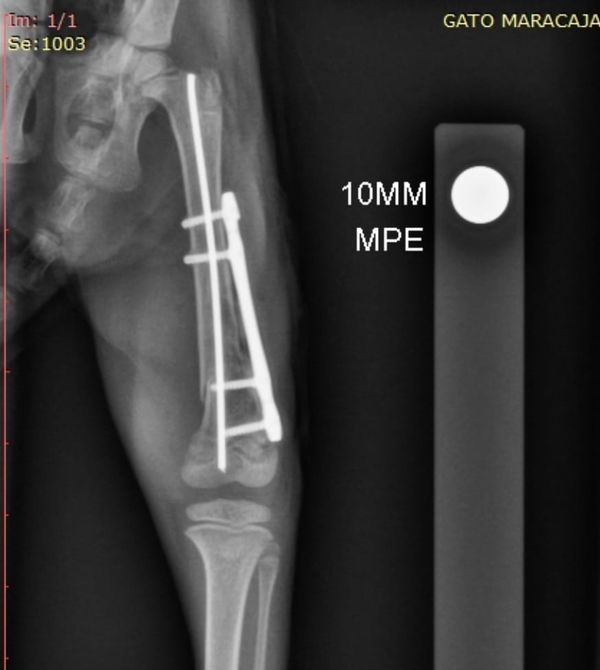

Diogo Garnica explicou que a cirurgia era extremamente complexa. A gata-maracajá tinha um fêmur quebrado, no qual uma placa de titânio precisou ser acoplada. O procedimento foi considerado um sucesso, mas o animal teve cinco paradas cardíacas e acabou morrendo.

Ele ressaltou que, por conta do tamanho do animal - que pesava aproximadamente 600 gramas - o procedimento era tratado como uma microcirurgia. Apesar de ter sido bem sucedido, a gata-maracajá não reagiu bem ao pós-operatório.